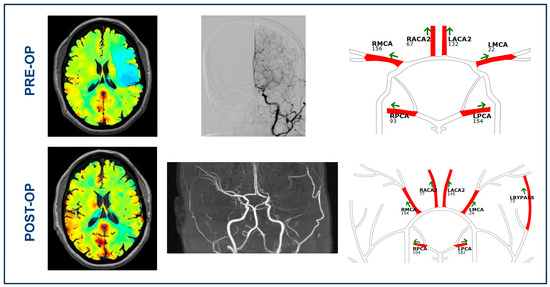

3.2. BOLD-CVR and qMRA-NOVA Imaging Data before Bypass Surgery

3.3. BOLD Cerebrovascular Reactivity after Bypass

3.4. qMRA-NOVA Values after Surgical Revascularization